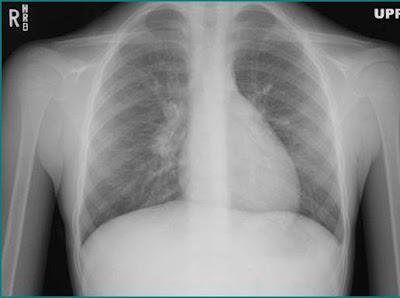

| Patient's chest x-ray |

Pneumomediastinum. Note the "continuous diaphragm sign" in the patient's chest x-ray caused by air collecting inferiorly between the heart and diaphragm. Other signs of pneumomediastinum to look for, but which are not readily noted on this x-ray, include a thin layer of air adjacent to the heart or aorta separated from the lung by a fine line representing the displaced parietal pleura and air in the subcutaneous soft tissues of the chest and neck.